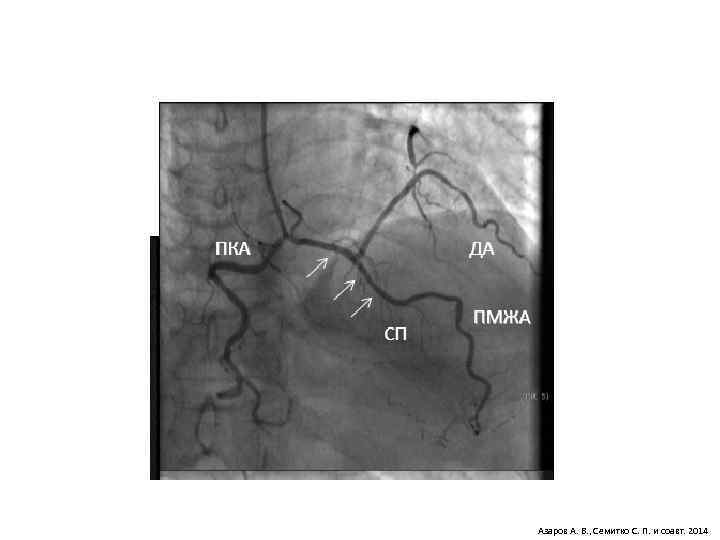

Азаров А. В. , Семитко С. П. и соавт. 2014

Миокардиальный мост Myocardial Bridge Азаров А. В. , Семитко С. П. и соавт. 2014